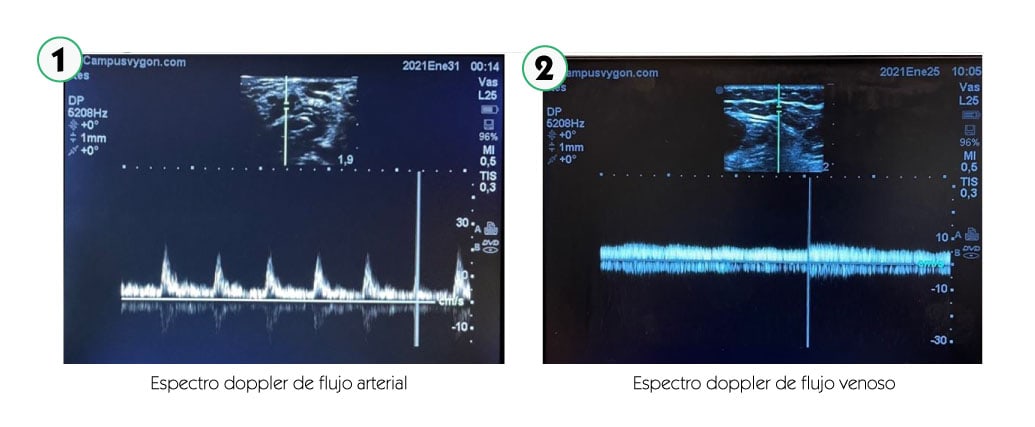

El doppler espectral consiste en la creación de una curva de velocidad versus tiempo, que representa la variación de la velocidad de flujo de los glóbulos rojos a lo largo del ciclo cardiaco, en un punto concreto de la imagen bidimensional o modo B. El tiempo está representado en el eje horizontal y la velocidad en el vertical.

Si el espectro de velocidades se sitúa sobre la línea base significará que el flujo del vaso sanguíneo estudiado se dirige hacia el transductor. Por el contrario, si el espectro de velocidades se sitúa por debajo de la línea de base, significará que el flujo del vaso sanguíneo estudiado se alejará del transductor.

Además del sentido de la sangre, la morfología del espectro nos informará del carácter del flujo del vaso estudiado. Así, si el flujo es pulsátil, habitualmente se tratará de un vaso arterial. Mientras que si el flujo es continuo o poco pulsátil, habitualmente se tratará de un vaso venoso.